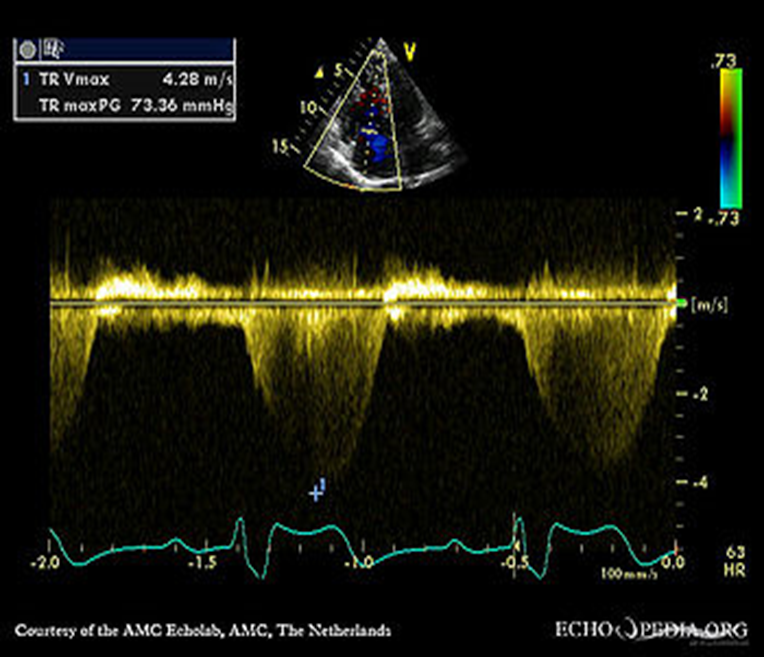

Right Ventricular Systolic Pressure (RVSP) is used to

RVSP is used to estimate right side pressures in the vessels leading to the lungs. This is used to determine pulmonary hypertension.

TR Vmax + RAP= RVSP

How to obtain the rsvp/spap

1. Place the CW cursor through the TR color jet

2. Measure the tricuspid regurgitant waveform to achieve the tr velocity

3. The machine will use the TR Vmax velocity and turn it into a pressure gradient. This is done by using the Bernoulli equation

If TR= 42MMHg+________

IVC=2.2

Add Sniff

=57

Ex? Since anything over 2.1 is abnormal and there was a sniff we add The high of 15. So 42+15= 57. If there was no sniff or the Ivc was 2.1 we would have added an 8 instead.

RVSP / Systolic pulmonary artery pressure (SPAP) determined by the TR

TR Max PG + RAP = RVSP/SPAP